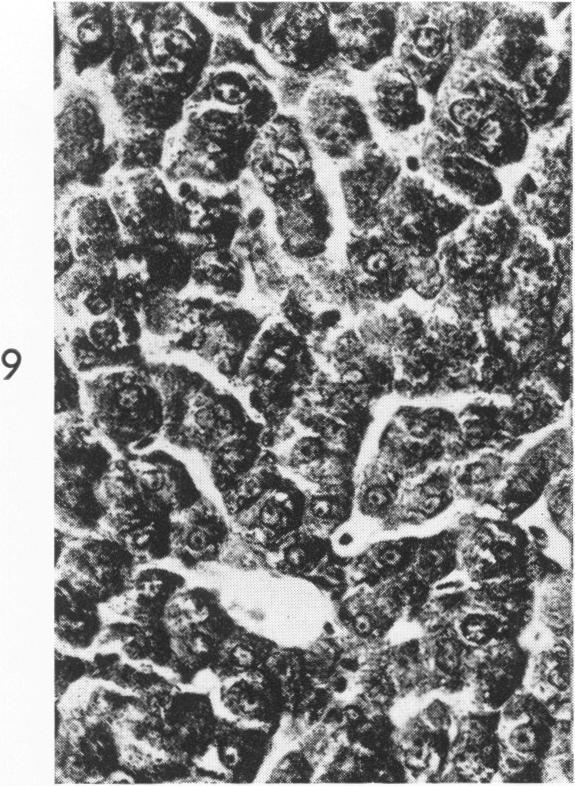

RESPONSE OF THE LIVER TO "TARGET" IRRADIATION.

Am J Pathol. 1965 Sep;47(3):339-51.